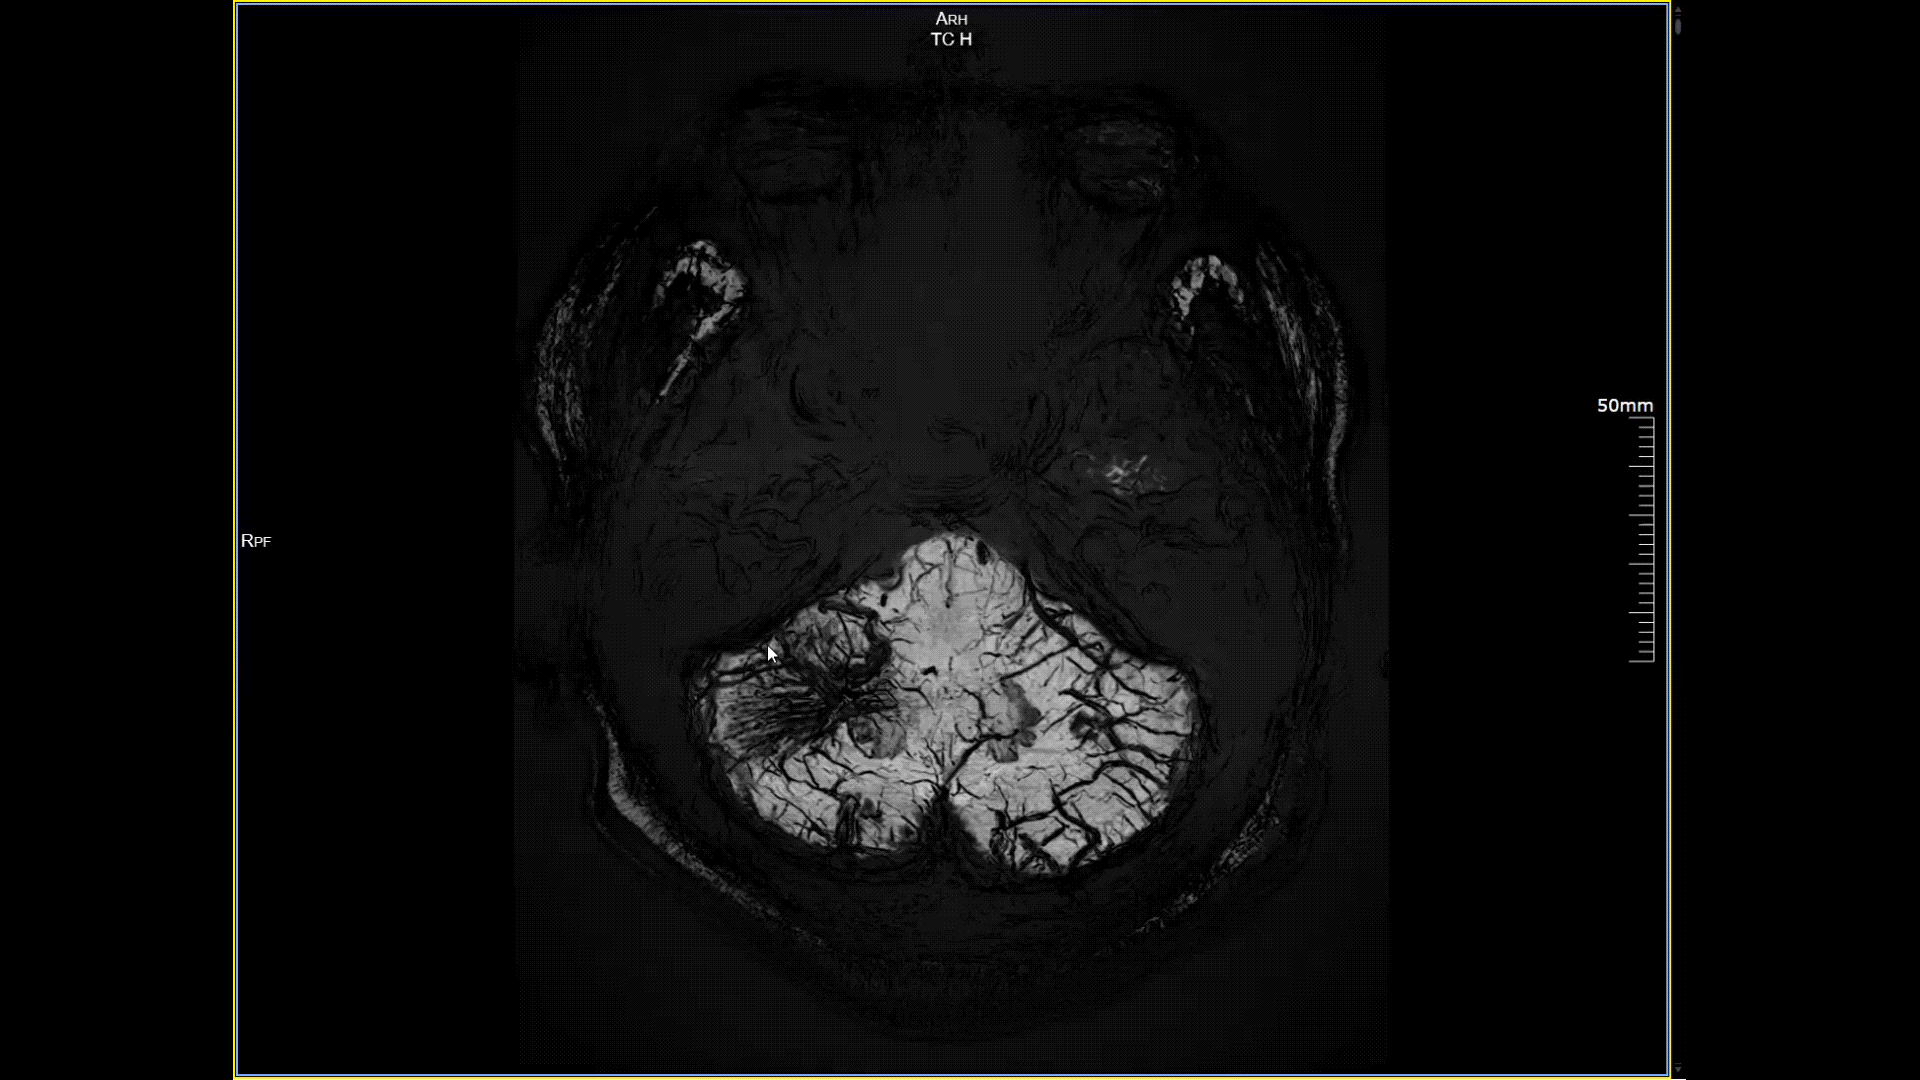

5.0T磁场强度远高于其他设备,使得氢原子核在磁场中的响应信号极大地增强。这就像在安静的房间里能听清细微的声音一样,高信噪比能让医生看到更微小、更模糊的病变结构。例如上述患者的检查,该设备可以呈现0.2x0.2毫米高分辨率的图像以及动态显示血管走行,使得病变血管的细微解剖结构、分布及其与周边脑组织的关系得以直观呈现,为临床医生进行精准诊断并制定后续治疗方案提供了重要的影像学依据。

磁敏感成像SWI,分辨率0.2*0.2mm